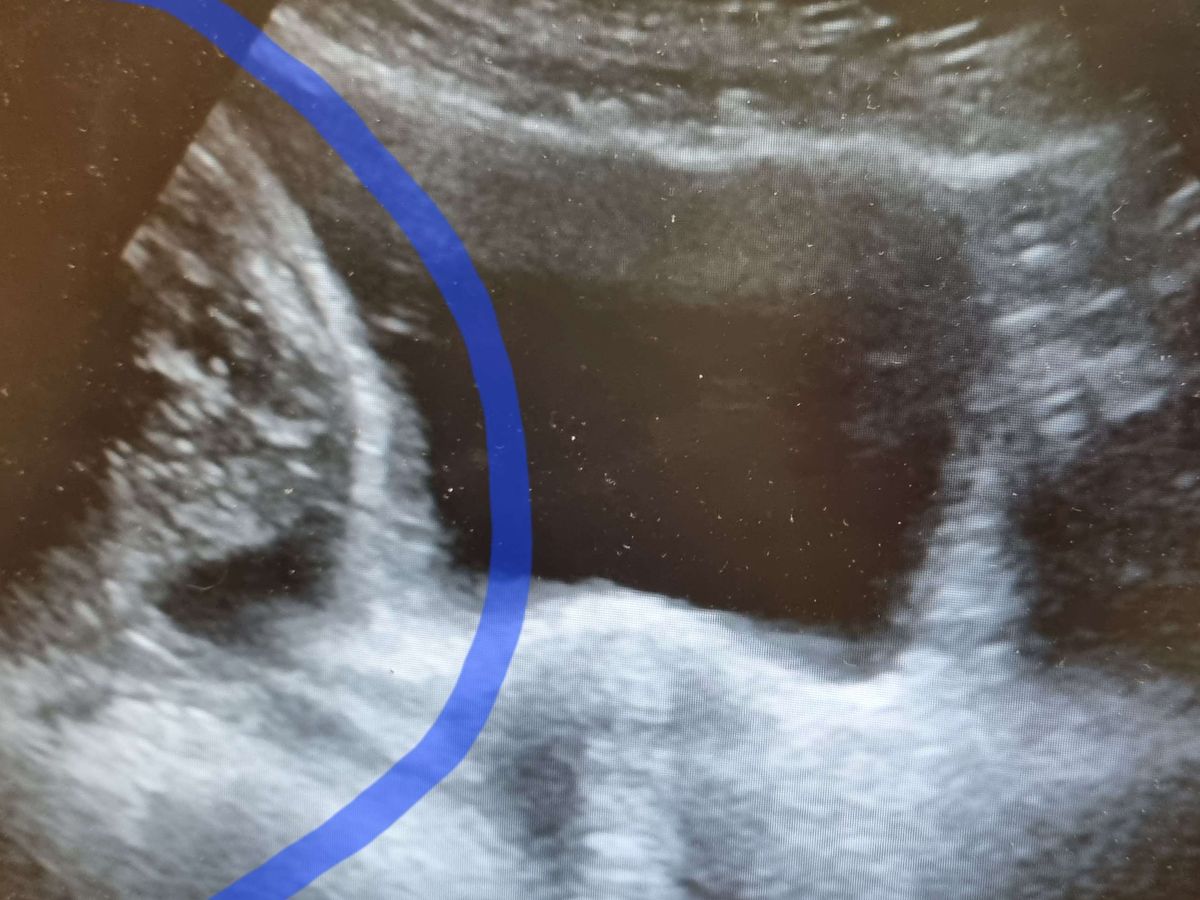

I have an ovarian tumour the size of a 4-month pregnancy which will need open surgery to remove.